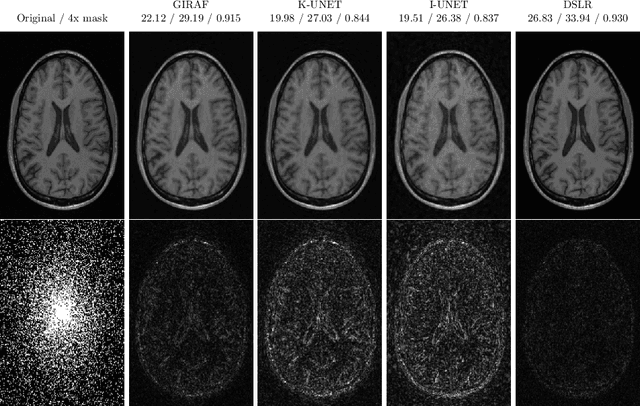

Abstract:In this chapter, we review biomedical applications and breakthroughs via leveraging algorithm unrolling, an important technique that bridges between traditional iterative algorithms and modern deep learning techniques. To provide context, we start by tracing the origin of algorithm unrolling and providing a comprehensive tutorial on how to unroll iterative algorithms into deep networks. We then extensively cover algorithm unrolling in a wide variety of biomedical imaging modalities and delve into several representative recent works in detail. Indeed, there is a rich history of iterative algorithms for biomedical image synthesis, which makes the field ripe for unrolling techniques. In addition, we put algorithm unrolling into a broad perspective, in order to understand why it is particularly effective and discuss recent trends. Finally, we conclude the chapter by discussing open challenges, and suggesting future research directions.